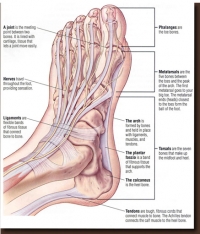

Arthritis is a term that is used to describe over 100 different joint conditions. At Superior Foot & Ankle Care Center we think it’s important for our patients to be informed about arthritic conditions—especially since each of your feet has 33 joints that need to be protected for your foot to function properly.

Did you know that the term arthritis refers to over 100 joint diseases and disorders? At Superior Foot & Ankle Center we want to pass on some information about this group of diseases that currently affects 1 in 5 adults in our country and approximately 300,000 babies, children and teenagers. Generally speaking, the risk of arthritis increases with age and more women than men are affected by these diseases. Your feet and ankles are prime targets for joint disorders, with 33 joints per foot. Common symptoms of arthritis include: pain, swelling and stiffness in joints, which limits range of motion and makes it difficult to move. There are 4 main categories of arthritis:

The most common causes of heel pain are Achilles tendinitis (back of the heel) and plantar fasciitis (bottom of the heel).

- Achilles tendinitis is an injury caused by the overuse of the Achilles tendon (the band of tissue that connects the calf muscle at the back of the lower leg to your heel bone). Achilles tendinitis is caused by repetitive or intense strain on the Achilles tendon; but the structure of the Achilles tendon also weakens with age, making it more susceptible to injury.

Symptoms: The associated pain usually begins as a mild ache in the back of the leg or above the heel after running or other sports activities. More severe pain may occur after prolonged running, stair climbing, or sprinting.

Treatment: Achilles tendinitis usually responds well to self-care measures. However, if your symptoms are severe or persistent, your doctor may suggest other treatment options, such as: over-the-counter pain medications, physical therapy exercises, orthotic devices, or surgery. - Plantar fasciitis commonly causes a stabbing pain that usually occurs with your very first steps in the morning. The pain usually decreases once your foot limbers up, but may return after long periods of standing or sitting. Plantar fasciitis is common in runners, people who are overweight, and those who wear unsupportive shoes.

Symptoms: Pain and inflammation of the thick band of tissue that runs across the bottom of your foot, connecting your heel bone to your toes.

Treatment: Most people can recover with conservative treatments after a few months. In some cases, your doctor may recommend other treatments, such as: pain medications, physical therapy, night splints, orthotics, steroid shots, stem cell injections, or surgery.